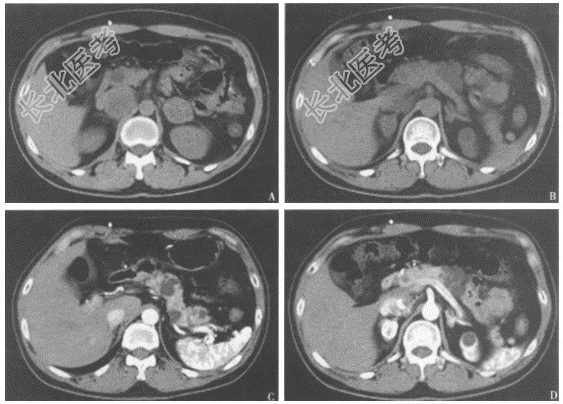

- 简答题3、患者的腹部+盆腔CT检查结果见图4、图5。患者目前可能的诊断是

- 简答题5、患者内分泌检查结果如下,24小时尿儿茶酚胺:肾上腺素(E)55.47μg/24h,去甲肾上腺素(NE)167.93μg/24h,多巴胺(DA)286.52μg/24h。血甲氧基肾上腺素(MN)65.8ng/L(14~90ng/L),血甲氧基去甲肾上腺素(NMN):4753.2ng/L(19~121ng/L)。患者肿瘤多发,为进一步从影像角度明确肿瘤的功能定位,并明确有无其他部位多发肿瘤,可选择的检查是

- 简答题6、¹³¹I-MIBG显像:双侧肾上腺区及右腹膜后异常放射性增高区占位病变,考虑嗜铬细胞瘤可能大。奥曲肽生长抑素受体显像:左肾上腺区及右腹膜后生长抑素受体高表达病灶,考虑为神经内分泌肿瘤。患者拟行手术治疗,在术前准备中,主要的可选药物是